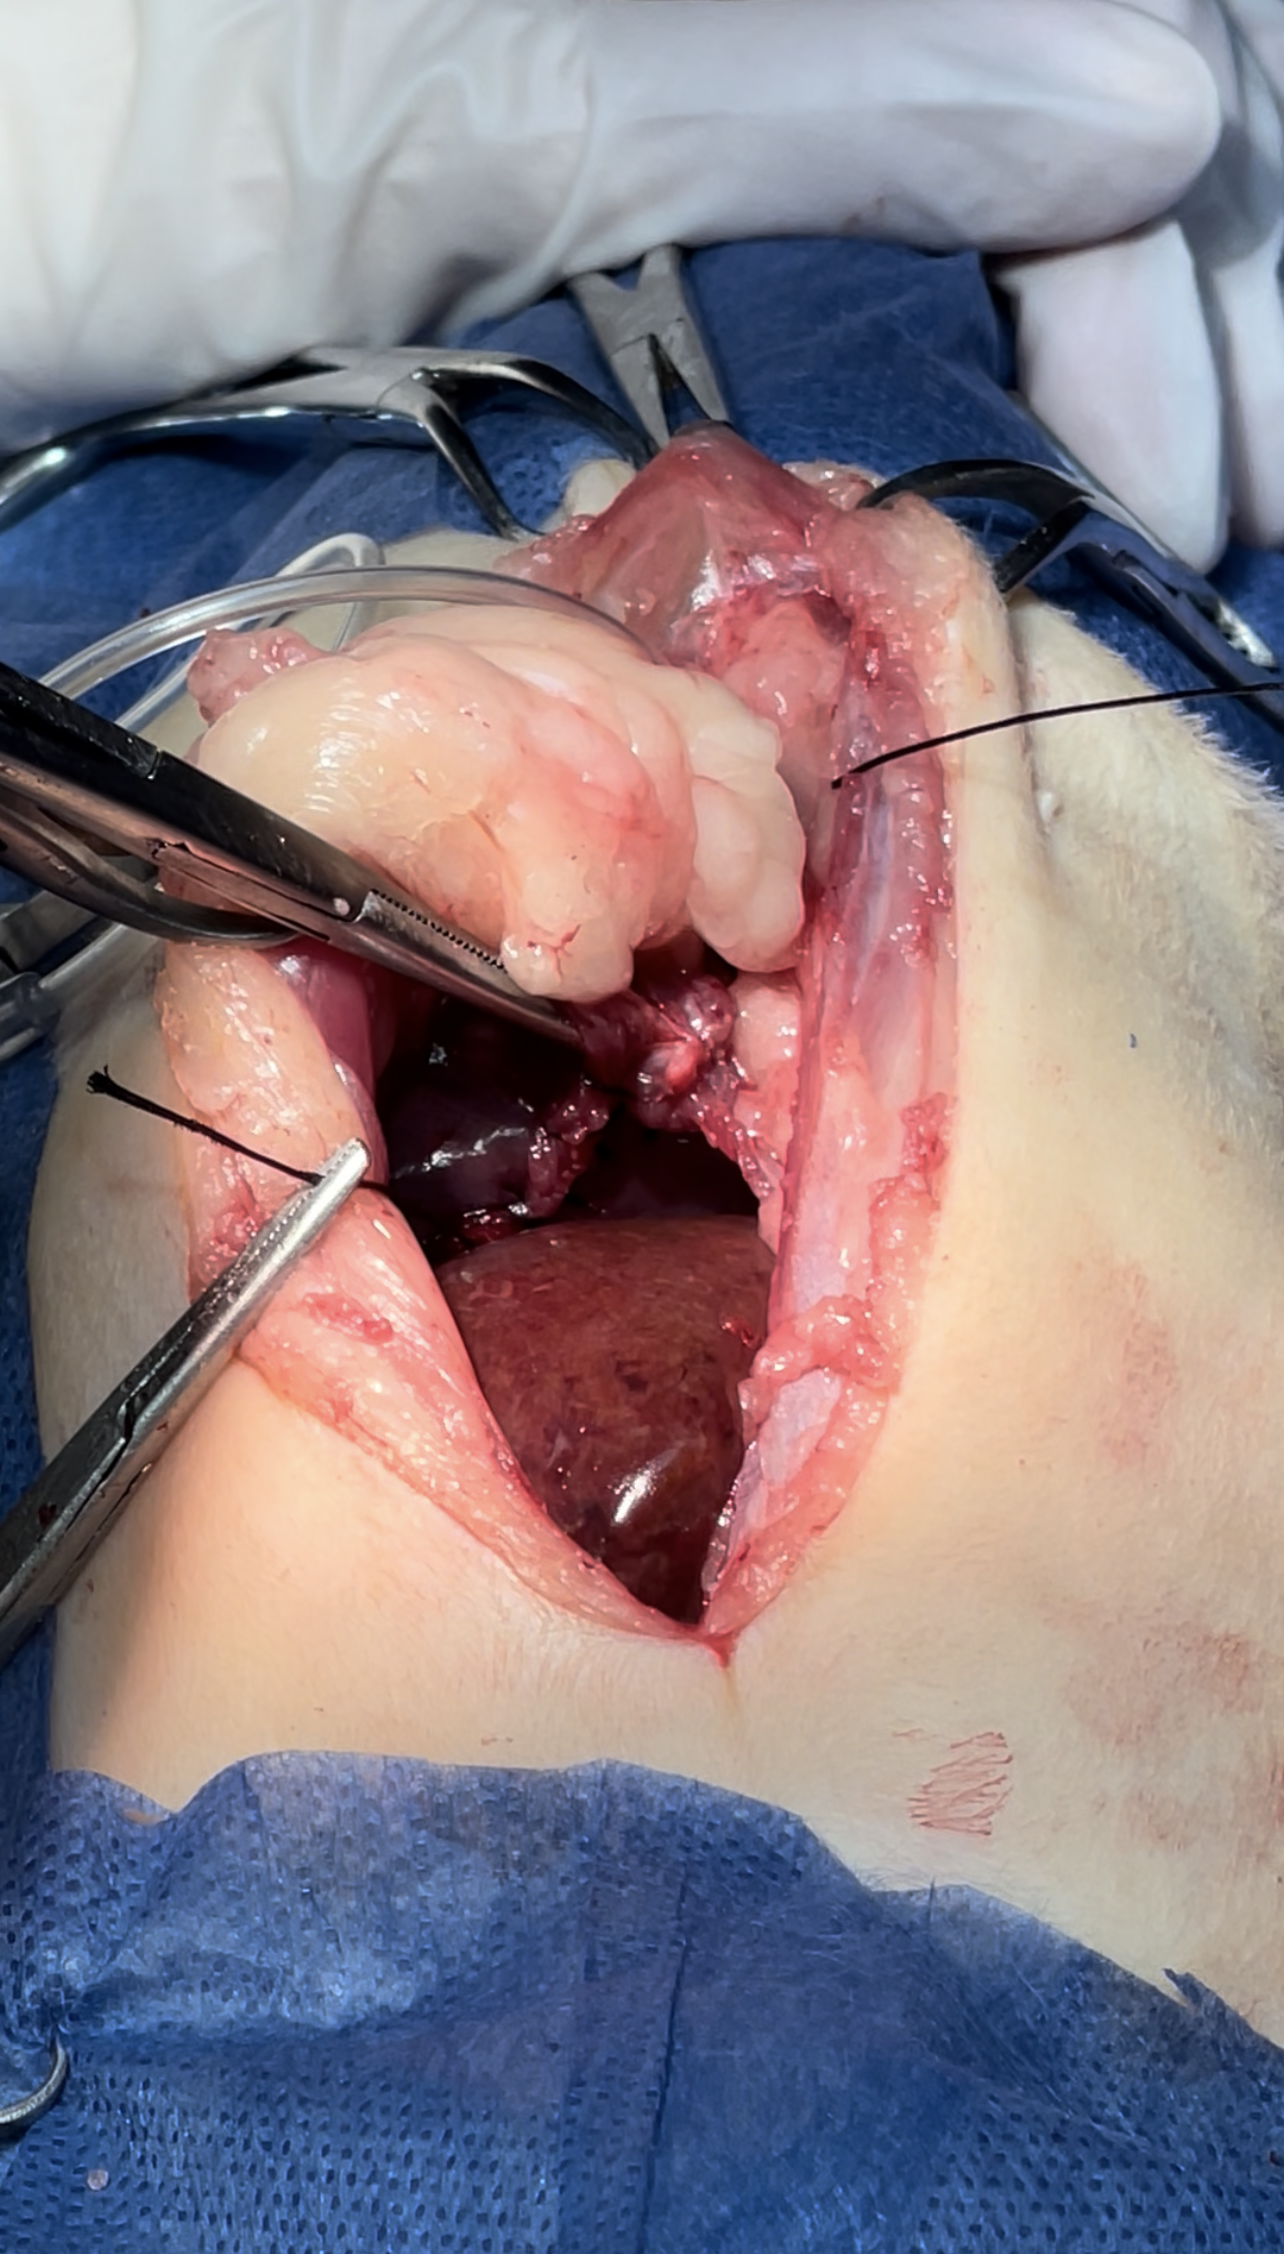

Dissection of the intraabdominal adhesive part of the live

Widening the herniation to allow organ exteriorization